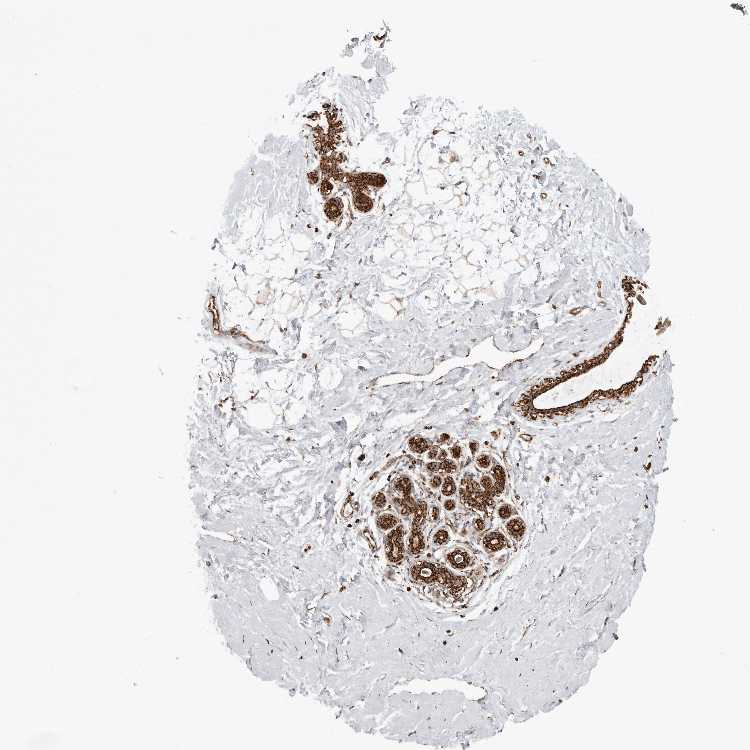

BREAST - Antibody stainingi

Antibody staining in the annotated cell types in the current human tissue is reported as not detected, low, medium, or high, based on conventional immunohistochemistry profiling in selected tissues. This score is based on the combination of the staining intensity and fraction of stained cells.

Each image is clickable and will lead to virtual microscopy that enables deeper exploration of all samples and also displays staining intensity scores, fraction scores and subcellular localization as well as patient and tissue information for each sample.

Antibody HPA026436Antibody HPA026451Antibody HPA026501

Adipocytes MediumLowNot detected

Glandular cells HighMediumNot detected

Myoepithelial cells HighMediumMedium